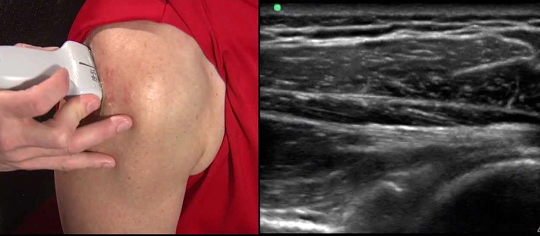

O exame auxiliar de diagnóstico a ser solicitado inicialmente é a Radiografia do ombro - que permite definir se existem alterações degenerativas ao nível do ombro e eventual presença de calcificações ao nível dos tendões ou imagens de esporões que podem contribuir para conflito com os tendões. O exame a ser solicitado na suspeita de tendinite é também a Ecografia. Esta permite definir se existe tendinite e eventual rotura parcial ou completa da coifa dos rotadores (a ser abordado noutro artigo), a sua extensão e localização ou se existe apenas inflamação local. Nos casos em que a Ecografia não é conclusiva, pode ser complementado o estudo por Ressonância Magnética Nuclear.